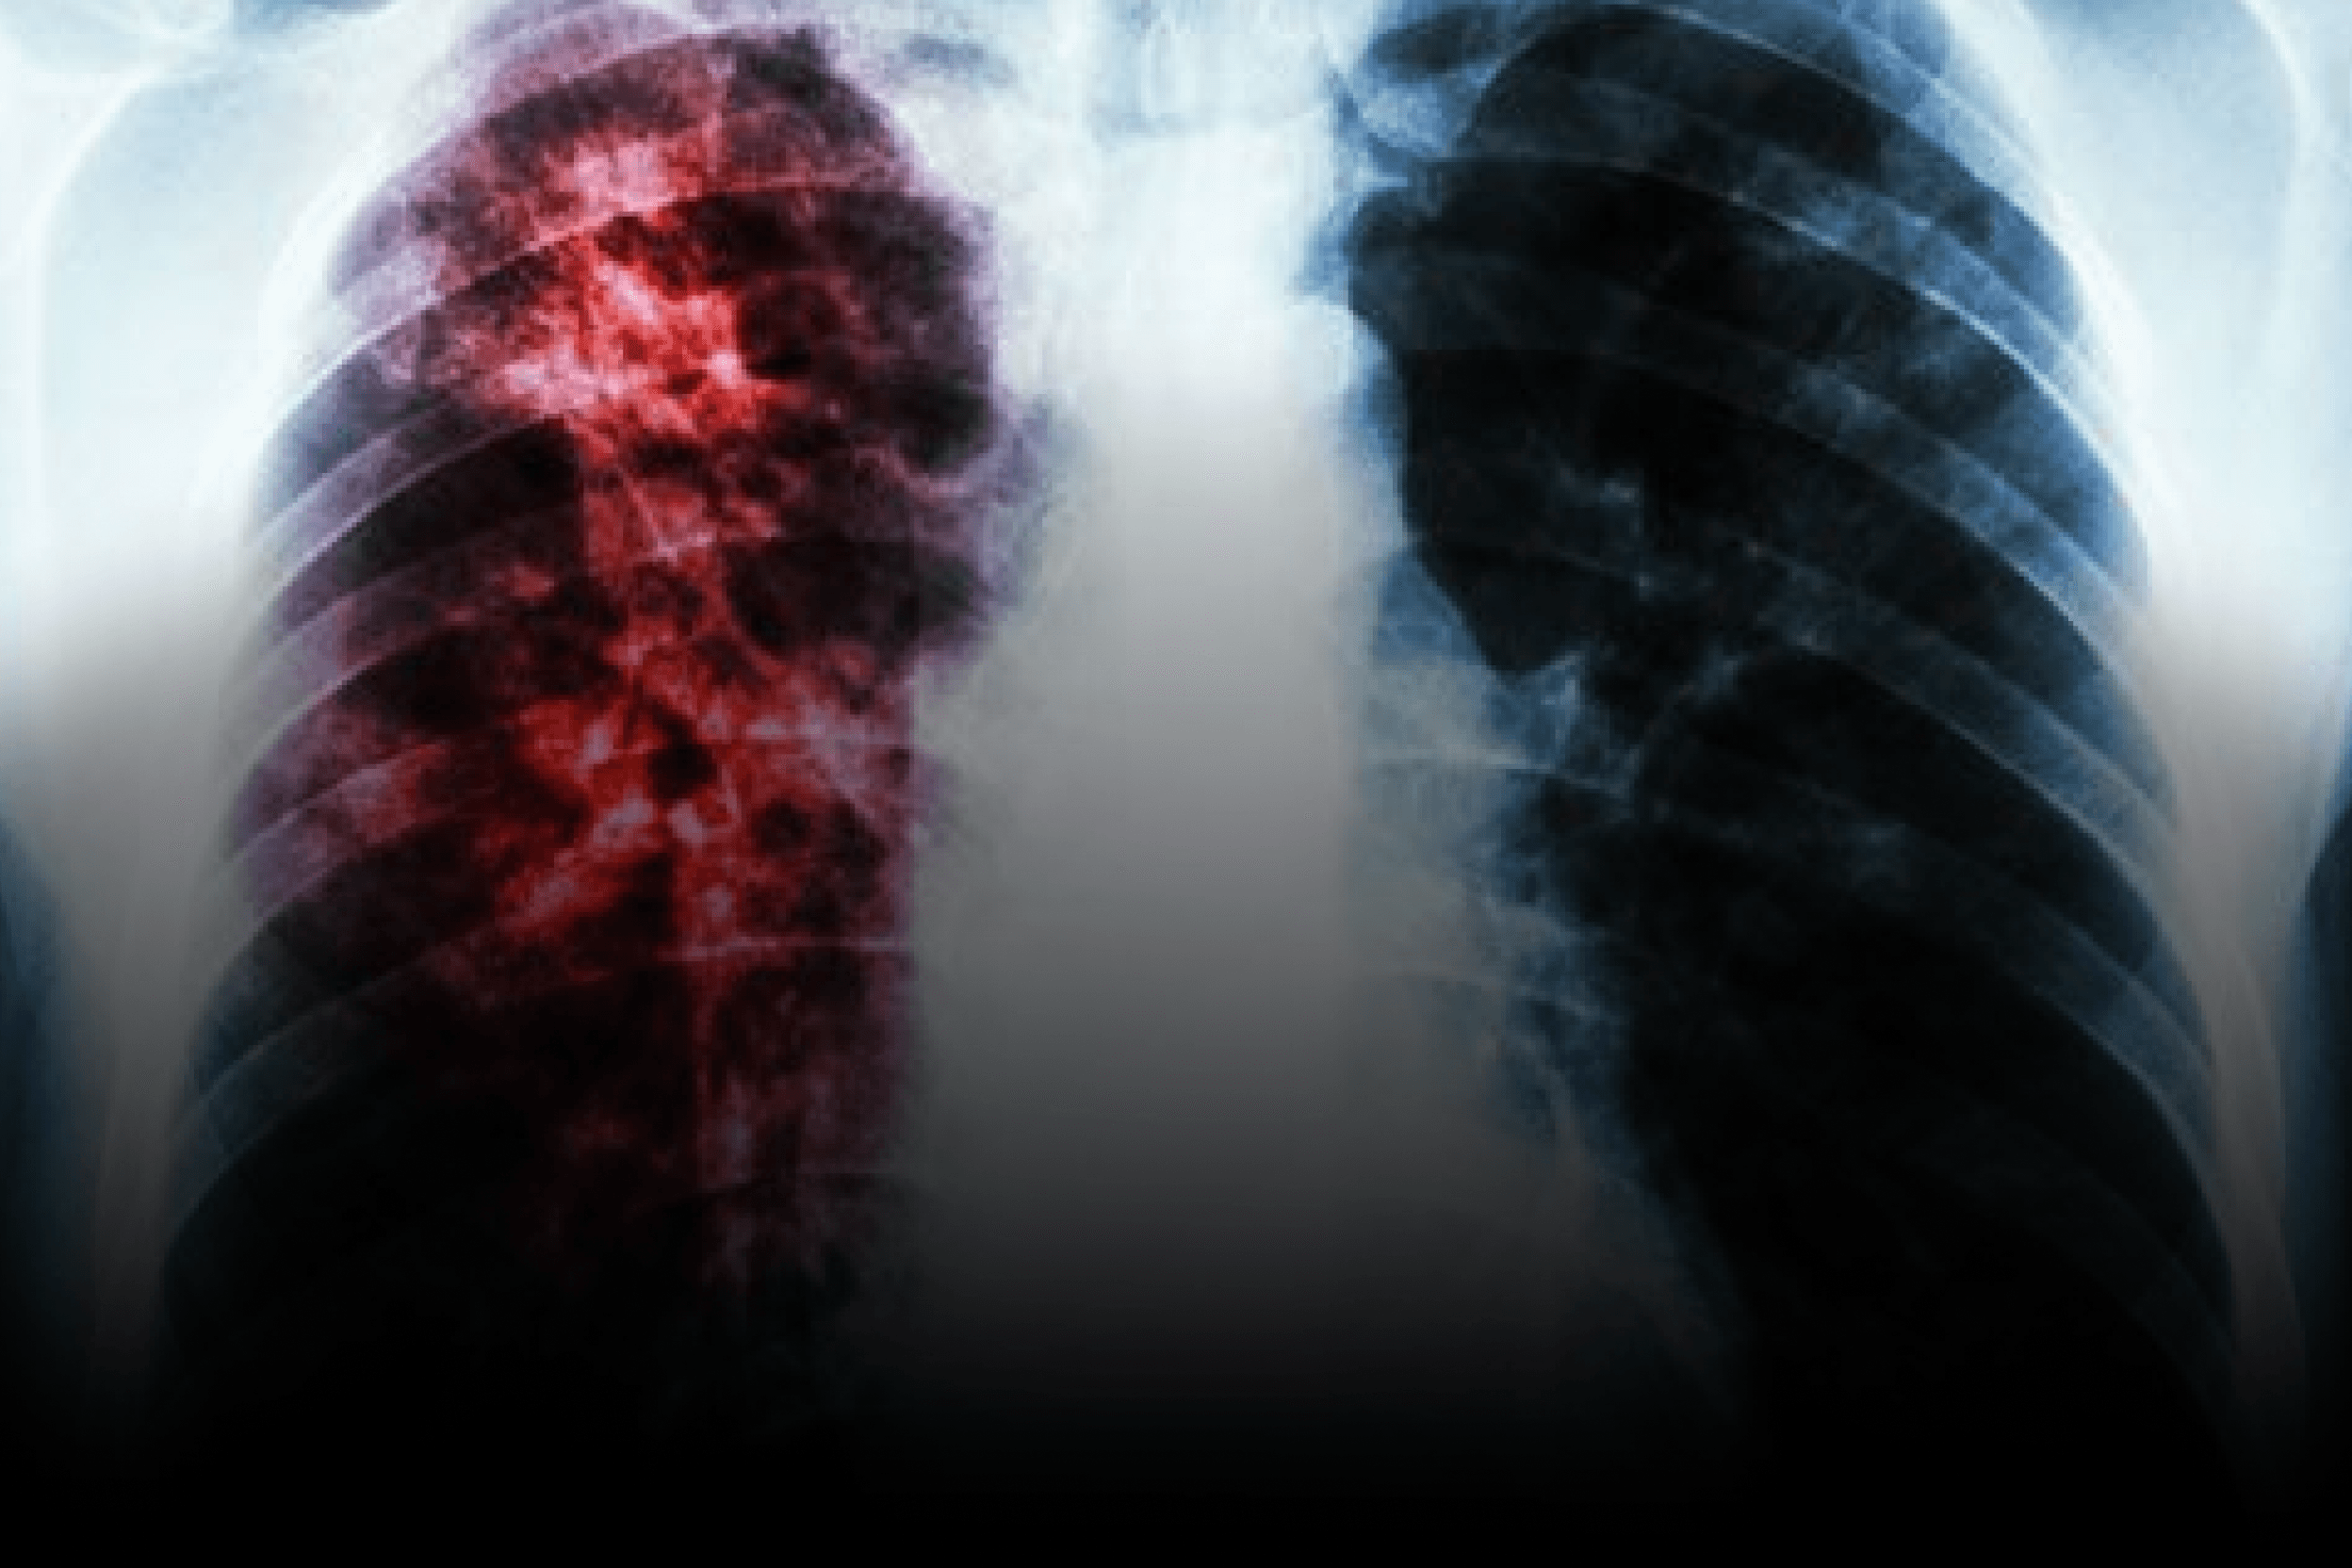

O futuro do combate à tuberculose resistente

Os resultados de fase 2 apresentados acima indicam que o novo antibiótico para tuberculose pode redefinir o cuidado no tratamento tuberculose resistente, ao combinar maior eficácia com segurança comparável. Em um cenário em que o Brasil permanece entre os países de alta carga e o mundo registrou ~10,6 milhões de casos de TB em 2022, a chegada de antibióticos inovadores é estratégica para reduzir tempo de negativação, simplificar esquemas e melhorar adesão.

Para adoção, dois eixos correm em paralelo: regulação e implementação. Regulatoriamente, espera-se avaliação de registro na Anvisa e, na sequência, análise de incorporação pela Conitec para uso no SUS, em linha com a expansão de esquemas totalmente orais (como o BPaL) já debatidos/implantados em serviços de referência. Do ponto de vista operacional, os pontos discutidos na seção anterior orientam a prática: definir critérios de elegibilidade, realizar exames basais (função hepática e ECG) e no primeiro mês, e ativar telemonitoramento semanal. Integrar checklists e alertas em protocolos clínicos digitais (PEC/e-SUS) facilita rastreabilidade, farmacovigilância e auditorias.